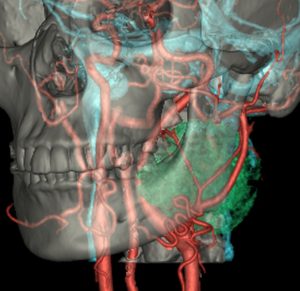

40歳の時に右頸部が腫れているのに気づいて発見され,耳鼻科で生検術され経過をみたものです。7年間の経過観察でかなり増大しました。症状は全くありませんでした。まだ腫瘍増大が止まらないので摘出することにしました。術前は舌咽神経鞘腫と診断することはできません。

手術中に中枢端で舌咽神経本幹に連続性がありここを切断して全摘出しました。それで舌咽神経鞘腫と確定診断ができています。

術後には無症状,他覚的な神経脱落症状はありませんでした。長い間かかって増大したので迷走神経などで代償機能が働いているのだと推定されます。

舌咽神経の末梢枝は,carotid sinusからの感覚神経を含むので,内頸動脈と外頸動脈の間に入り込むように増大することがあります。